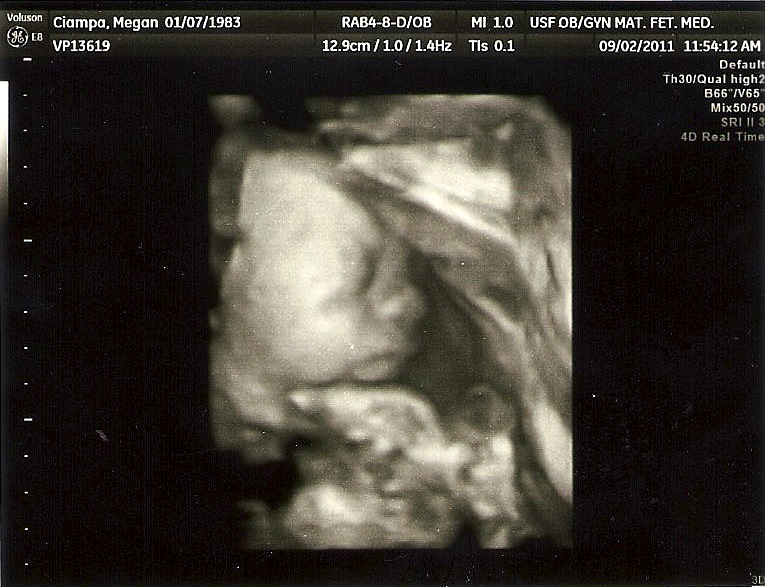

Sleep always has been a war zone for her and us. We've drawn lines many times before, and found success, only to let something creep in that sets us back several stages. Especially at naptime. As I said before, she puts up more of a fight with me at naptime than she does with Greg at bedtime. Now that I'm pregnant, however, and due within the next

three months(!), it is imperative that we press the "reset" button on a few of these areas so that life for everyone in our household will hopefully be a bit easier to manage especially when there's one more added to the mix.

| Summer 2011 |